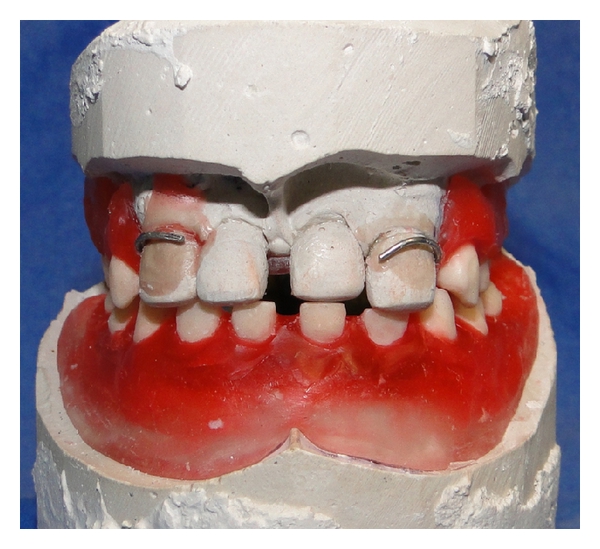

The artificial teeth needed for the denture were fabricated at the lab with a suitable shade of heat cure acrylic resin (Figure 8). The teeth shaped as primary teeth were arranged on the wax occlusal rim with spacing to simulate the natural spacing expected for the patients’ age. The artificial teeth were arranged in wax for trial evaluation. Tooth positions, occlusal relationships, and the necessary corrections were made before processing the dentures after the prosthesis wax try-in (Figure 9).